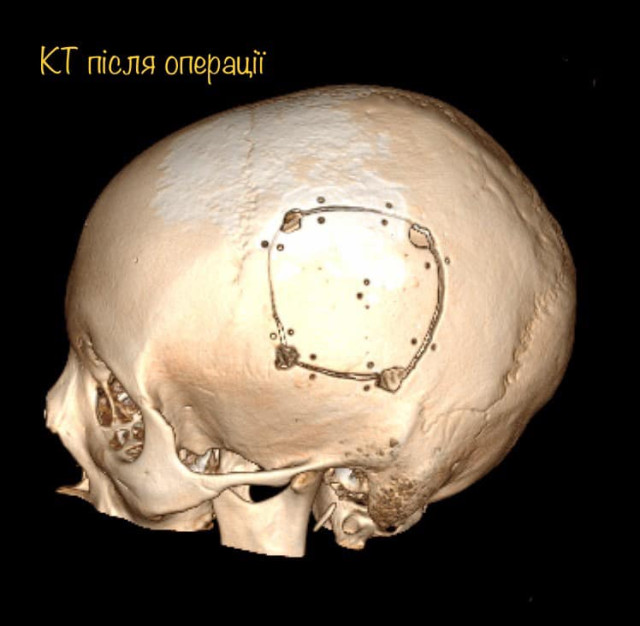

І хоча пухлина, як розповідає Михайло Ловга, знаходилась всього в кількох міліметрах від центру мови, і лікарі ледве-ледве знайшли безпечну ділянку мозку, через яку вдалось видалити пухлину – результат лікування чудовий. Діана вже через годину після операції вільно розмовляє, звичайно рухає усіма кінцівка і ні на що не скаржиться.